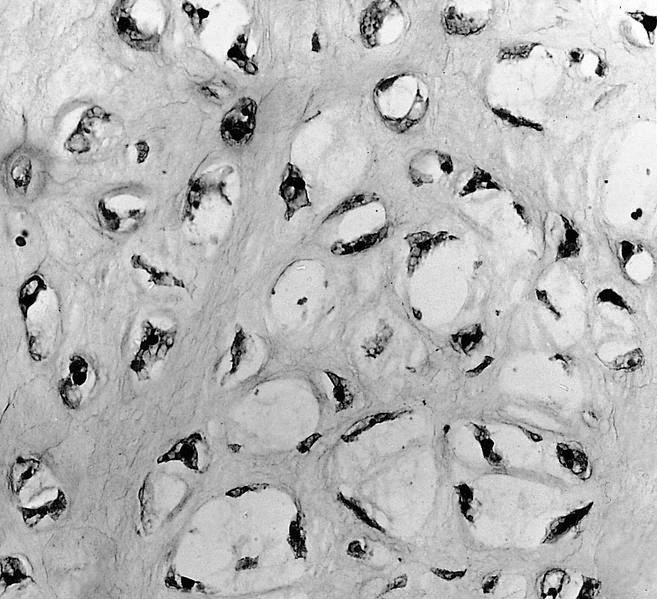

Microscopic (histologic) description

- Cap composed of mature hyaline cartilage with overlying fibrous perichondrium

- In young patients, transition between bone and cartilage cap resembles growth plate, showing endochondral ossification into mature bone; cartilage cap diminishes and may essentially be absent in older adults

- Marrow elements may be present within bony stalk; marrow space / cancellous bone contiguous with that of the native bone

Microscopic (histologic) images